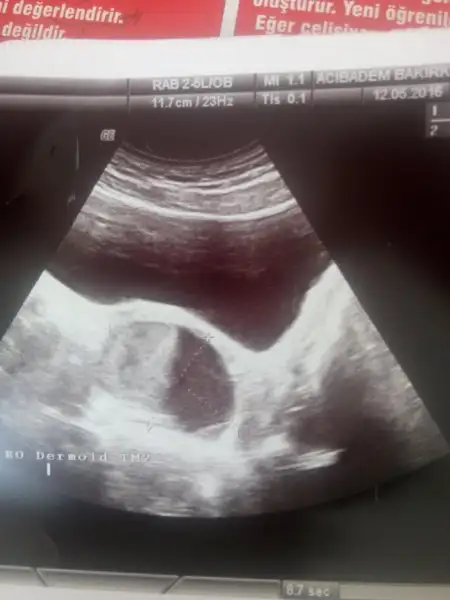

Simdi doktordan geliyorum kistim hala ayni boyutta duruyor regl doneminde bakti hala duruyor.Muhtemelen dermoid kist dedi icinde sac kil tuy vardir besbucuk cm dedi.bu kist nette okudum ameliyatla mi aliniyor illa tedavisi yok mu :(suan doktor ameliyat demedi ama bir regl donemi daha atlat ona gore bakacagjz tedavi plani dedi galiba ameliyati kastetti.cok uzgunum suan ya:(

Arkadaar cevap verirseniz cok sevinicem doktorum yumurtaligimda kist oldugunu soyledi ve adet olamiyorum.2014 yilinda dogm kntrol hapi vermisti 31 ocak en fazla 6 ay kullanabldm cunku beni hastsnelk ediyoe refluyi tetikliyor uc sise serim tiyordm.ozaman teshis polikistik over dedni 3 cm di kisler sogan kurude yaptim ara ara duzenli oldugumsa sevinjhoedum. ufak uifak kistler brsy olmaz dediler.smdi aradan 2 sene gecti ve adetlerm yine duzensiz karnjmda agri hatta sag kasigimdma apandist deyip gittim ki su sonucla karsilastim.ultrason sonucu

Sag overde; 53x43x60 mm boyutlarinda, kalin duvarli, kalın septasyonlar içeren yoğun içerikli komplike kist.